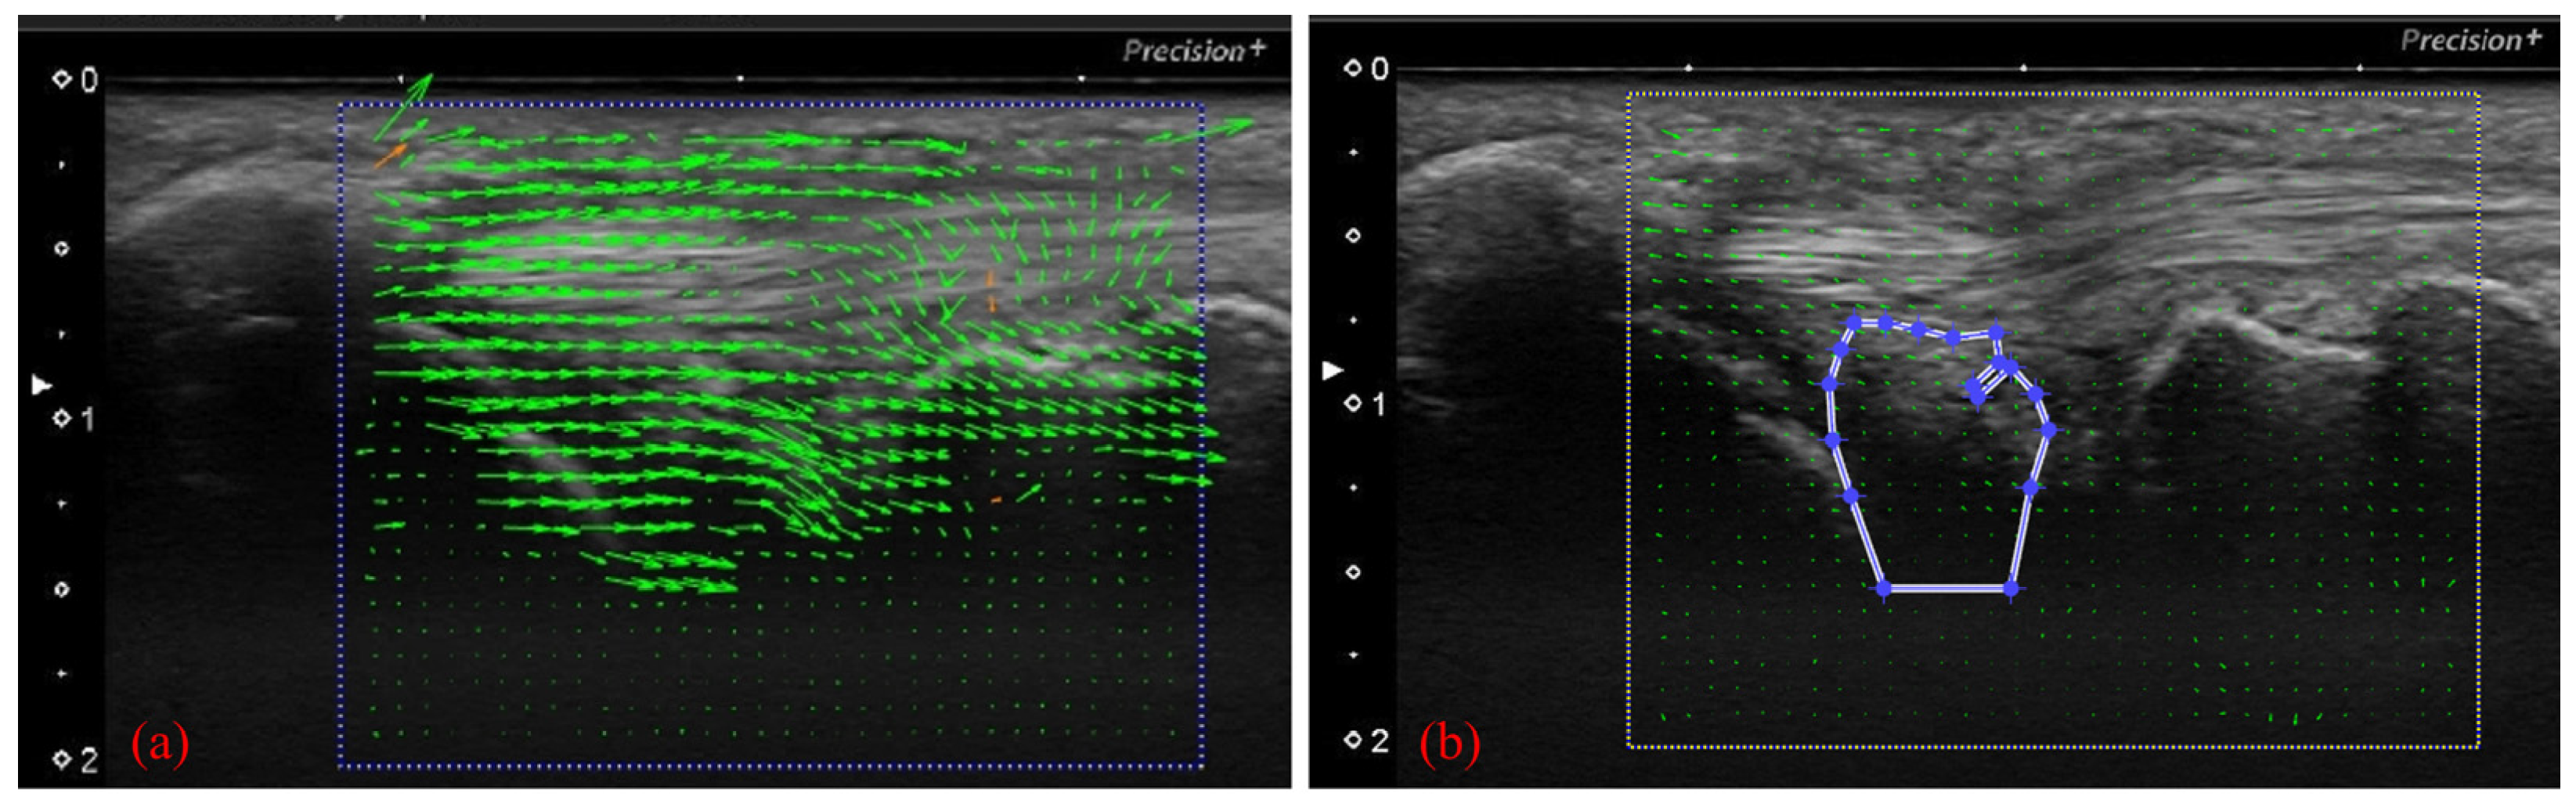

To perform motion analysis, TFCC visualization was performed with the forearm in pronation. Under these views, the wrist was actively moved from 15 degrees of radial deviation to 25 degrees of ulnar deviation at a 60-rounds-per-minute rhythm that was paced by a metronome (Figure 3). The same examination was performed twice per wrist. All US images were evaluated by two examiners (both senior orthopedic surgeons). As described previously, the articular disc was detected as a hypoechoic area [5]. Its area of measurement was defined by four lines as follows: proximal end of the articular disc, distal end of the articular disc, ulnar collateral ligament, and joint space between the lunate and triquetrum (Figure 4a). The area was calculated by using ImageJ software (USA National Institutes of Health [NIH], Bethesda, MA, USA), which is a public-domain Java-based image-processing software developed at the United States NIH [12]. Briefly, the areas of the defined articular disc were manually plotted and measured by using the Image J measurement tool (Figure 4b). Then, a comparison of the area of the articular disc between radial and ulnar deviation was performed. Furthermore, a correlation between patient height and the mean area of their articular disc was calculated. Measurements were performed by three orthopedic surgeons, using Image J. To confirm reproducibility, we calculated the intra-rater correlation coefficient and the inter-rater correlation coefficient by using these measurement results. Using the same images, the velocity magnitude of the articular disc displacement or ECU motion was analyzed by using PIV fluid measurement software (PIV lab. Version 2.36, add-in software from MATLAB (Mathworks, Natick, MA, USA)) [9]. Briefly, two regions of interest were set at the articular disc and ECU tendon (Figure 5). We edited all US movies into 30 static images per second. The pixel displacement between two sequential images was measured, and the velocity magnitude of the structure inside the region of interest was subsequently calculated. For the articular disc, the u-component, which comprises the longitudinal movement of the articular disc, was calculated. The v-component, representing the overall axial movement of the articular disc, was also calculated. Since the u- and v-components show positive and negative values depending on the direction of movement, the evaluation was added to the absolute values. PIV measurements were performed twice, with three examiners performing the measurements. The inter-rater and intra-rater correlation coefficients were evaluated.

Figure 5.

(a) Analyzing velocity magnitude image by using particle image velocimetry (PIV) fluid measurement software. With the US images, setting the articular disc and ECU tendon as regions of interest of the PIV. (b) Specification of the area to be measured (articular disc).

For the control group, the mean area of the articular disc was 25.37 ± 2.74 mm2 on radial deviation and 27.66 ± 2.89 mm2 on ulnar deviation. The areas during ulnar deviation were statistically larger than those during radial deviation in all cases (p < 0.01, p = 0.00009). The disc area was correlated with height in all volunteers of the control group (correlation coefficient, 0.75; p = 0.000135). For the injury group, the mean area of the articular disc was 29.55 ± 4.07 mm2 on radial deviation and 26.65 ± 3.98 mm2 on ulnar deviation. In contrast to the control group, the areas during radial deviation were statistically larger than those during ulnar deviation in patients with Palmer type 1B TFCC injury (p = 0.018) (Figure 6). For this assessment, the inter-rater reliability was 0.79, and the intra-rater reliability was 0.79. The average velocity magnitude of the articular discs, when measured by PIV, was 1.95 ± 0.48 mm/s for the control group and 3.21 ± 1.38 mm/s for the injury group. Representative images of the PIV measurement of the articular disc data for the control and injury groups are shown in Figure 7. The average velocity magnitude of the articular disc was significantly higher for the injury group (p = 0.011), and that of the ECU tendon was 1.94 ± 0.54 mm/s for the control group and 2.45 ± 0.49 mm/s for the injury group. The velocity magnitudes of both the articular disc and the ECU tendon were significantly higher in the injury group than in the control group (p = 0.042). Additionally, the average of the u-component of the articular disc was 1.55 ± 0.42 mm/s for the control group and 3.34 ± 1.07 mm/s for the injury group, showing a significantly higher u-component in the injury group (p = 0.00057). The average of the v-component of the articular disc was 0.75 ± 0.31 mm/s for the control group and 0.46 ± 0.09 mm/s for the injury group, showing no significant difference between the two groups (Figure 8). However, the vector directions during radial and ulnar deviation were different between the control and injury groups. The control group moved toward the direction of the US probe during ulnar deviation, whereas the injury group moved toward the direction of the US probe during radial deviation (Figure 7). This result is consistent with the measurement of the area of the articular disc. The inter-rater reliability was 0.89, and the intra-rater reliability was 0.97 for this assessment.

Figure 7.

Flow PIV fluid measurement software of (a) the control model and (b) the TFCC injury model. (c) Representative data of the time series data on the velocity magnitude of the articular disc. Flow velocity was significantly higher in the injury group during both radial and ulnar deviation. (d) Representative data of the v-component. The v-component is moving in different vectors in the control group and the injury group.